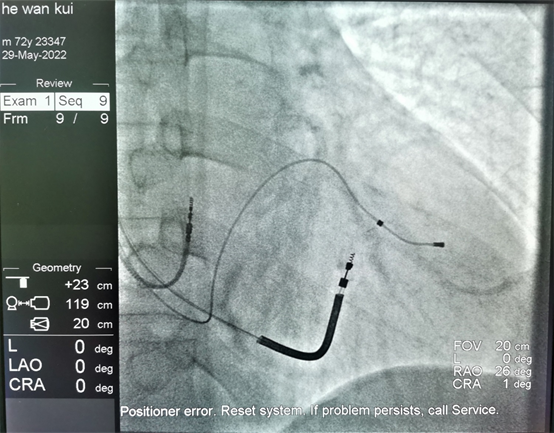

该病人患有心肌梗死多年,此后反复发生心力衰竭,近期多次因室速发作,就诊于各大医院,本次因室速发作不能终止收入我院心内二科,入院后予电复律将心律转复窦性心律。病人心脏彩超结果提示左心明显扩大,EF值为27%(正常值应大于50%),心电图提示QRS波群宽度为了144ms(提示有心脏收缩不同步的表现)。综合分析患者病情,认为患者为植入三腔ICD的适应征,既能预防因室速或室颤发作导致的猝死,又能通过双室起搏最大程度纠正患者的心力衰竭。手术过程非常顺利,右房、右室及左室电极分别成功植入了理想的起搏部位。该起搏器的植入将会有效的预防病人猝死的发生,并能最大程度的改善患者的心功能。